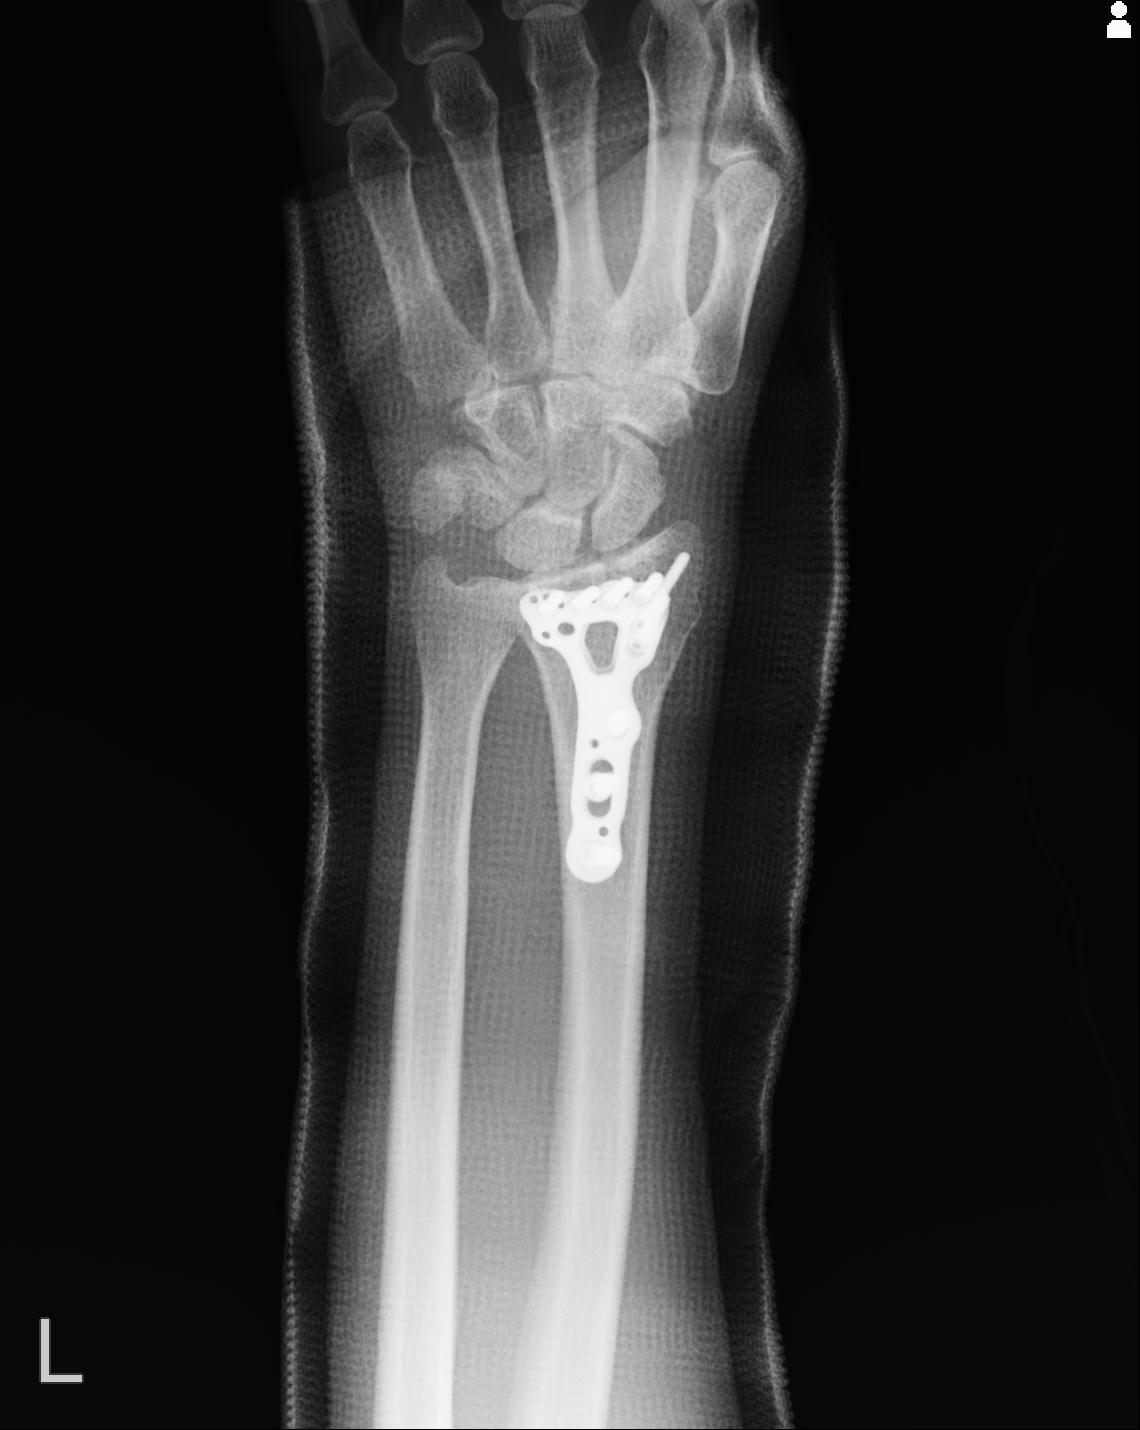

46666 1/23 両股正面+軸と右手関節 2R 76歳女性 右橈骨遠位端

50435 1/4 1/15 手関節 4R 17歳女性 右橈骨遠位端

102739 12/30 1/5 左手関節 4R 92歳女性 橈骨遠位端

101290 1/4 5/21 5/20 手関節 2R 17歳男性 橈骨遠位端